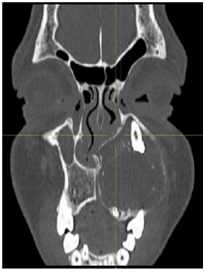

Panoramic Radiographic was obtained shows a large unilocular radiolucency on the left side of the maxilla, extending from tooth #22 to #26. Unerupted tooth #23 was present inside the lesion. Computed Tomography (Figure 2) (Figure 3) of facial bone was obtained shows well circumscribed unilocular radiolucency and radiolucency involves the crown of unerupted tooth #23. Based on the history and clinical features and radiographic evaluation dentigerous cyst and adenomatoid odontogenic tumour was made as provisional diagnosis. Other strictly radiolucent lesions worthy of consideration are keratocystic odontogenic tumor, ameloblastic fibroma, odontogenic myxoma, or central giant cell tumour as well as unicystic ameloblastoma which is common in this age.

Figure 2 Initial paranasal sinus computed tomography axial view.

Figure 3 Paranasal sinus computed tomography coronal view.

Panoramic Radiograph does give a comprehensive view of the lesion, but a multi-slice CT scan provides the extension of the lesion in all directions besides showing dental involvement, as in this case it revealed intracapsular presence of canine tooth which couldn't hence be saved. It also showed involvement of the maxillary sinus and aided in treatment planning. Quality and quantity of the scattered radiopaque foci can also be well appreciated on the CT scan. CT scan provides proper extensions of the AOT, reveals proximity to the vital structures which aid in the preoperative evaluation, provisional diagnosis, planning and execution of the surgical procedure.